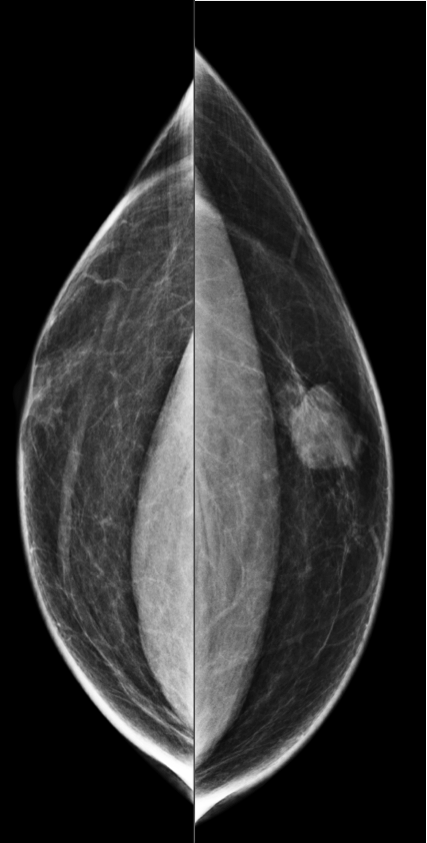

A 45-year-old asymptomatic woman with no family history of breast canc...

Read More